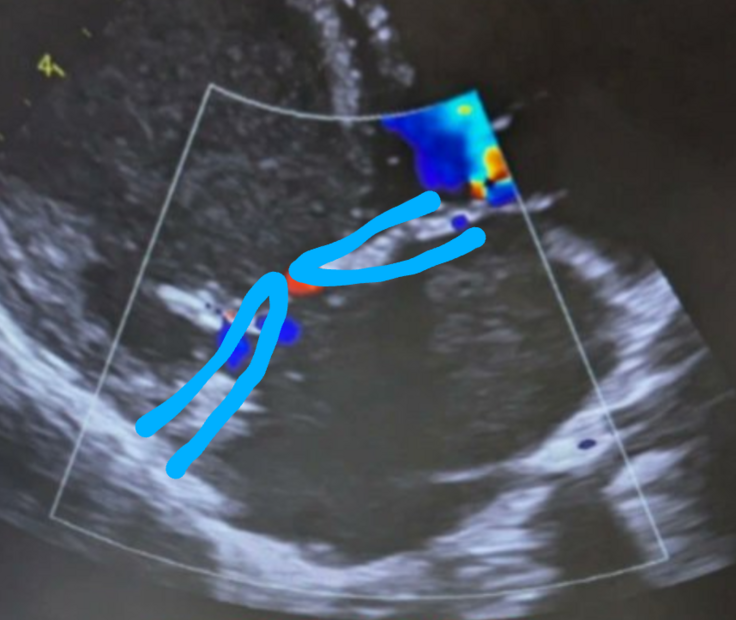

▼ここが「僧帽弁」という血流を制御する場所なのでこの弁が壊れた子が僧帽弁閉鎖不全症と呼ばれます。ここを人工的に補うのが僧帽弁形成術です。